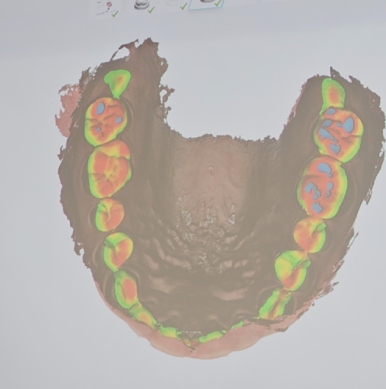

저희 병원은 스캔해서 임프레션 안하는데요?

이런 치과 많을 겁니다.

저도 얼마전 단국대학교에거 좋은 기회로 가장 최근에 나온 스캐너 기계를 실습하러 다녀왔는데요.

틀니도 스캐너로 인상채득하고,

교합도 스캐너를 통해 정밀하게 조정도 가능하답니다!

점점 AI시대가 도래하면서 디지털이 발달하고 있지만,

그럼에도 여전히 아날로그 방식으로

진료하는 곳도 많고,

무엇보다 디지털을 이해하고 알기위해서는

아날로그인 러버인상채득을 먼저 이해하는게

중요합니다. 아무리 좋은 스캐너라도 어디가 어떻게 잘나와야 하는지 모른다면

아무 소용이 없기 때문이죠,